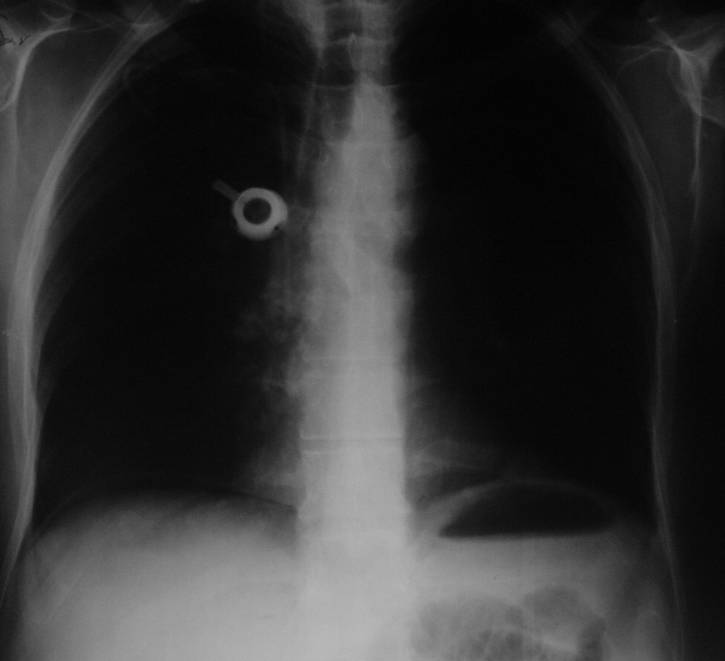

Konvansiyonel Radyoloji

• Direkt grafiler genellikle akut karın sendromu varlığında ya da akut tıkanıklıkta.